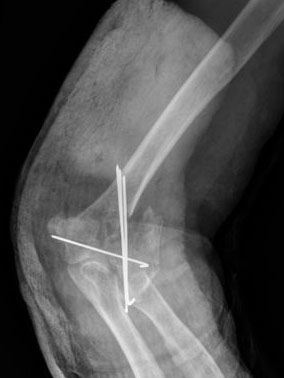

Fractura supracondílea de codo.Tras reducción y osteosíntesis.

Fractura supracondílea de codo. Tratamiento con agujas.